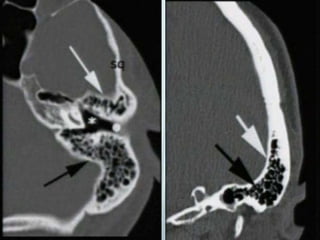

EPITYMPANUM

 Above plane from lower scutum to tympanic VII

 Malleus capitis and short process of incus

 Prussak epitympanum recess

MESOTYMANUM

 Tympanic cleft proper dampens sounds

 Manubrium of malleus

 Long process of incus

 Superstructure and foot plate of stapes

OUTER AND MIDDLE EAR DISEASE

 Malignant otitis externa

 Chronic otitis media

 Cholesteatoma

 Post surgical ear COM/CS

Middle ear

effusion

Cholesteatoma